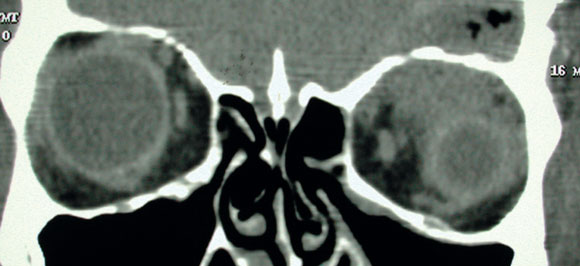

Non-contrast computed tomography (CT) of the brain revealed two minute areas of high density in the left frontal lobe, interpreted as evidence of early infection. CT of the orbits revealed left-sided swelling of the subcutaneous soft tissue, interpreted as preseptal cellulitis. A fracture of the left orbital roof was also noted adjacent to a superior orbital phlegmon (Box 1A).

However, as the cerebrospinal fluid appeared normal on microscopy and biochemical examination and showed no growth on culture, the initial diagnosis was questioned. Magnetic resonance imaging of the brain and orbits was performed the day after presentation. This showed a 5 cm tract extending obliquely from the roof of the left orbit into the white matter of the left frontal lobe, associated with a fracture of the orbital plate of the frontal bone (Box 1B). Inflammatory changes, presumed infective, were noted superiorly within the left orbit, resulting in proptosis.

1 Imaging in a patient with an orbital fracture

A. Computed tomography showed a fracture of the roof of the left orbit (F), adjacent to a superior orbital phlegmon (P).

B. Subsequent magnetic resonance imaging showed a 5 cm oblique tract extending from the fracture of the orbital plate of the left frontal bone into the white matter of the left frontal lobe.